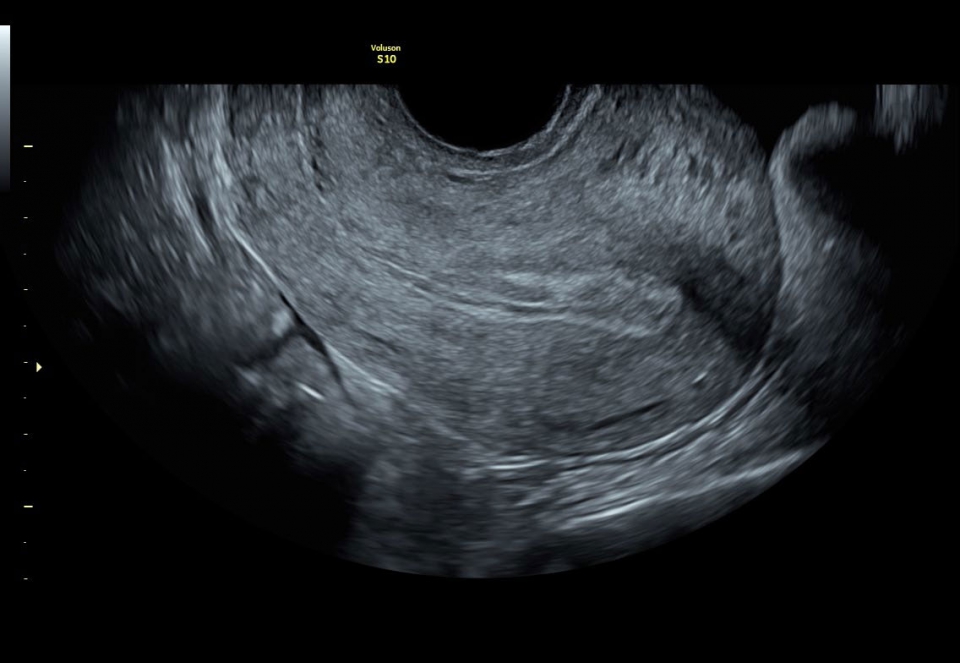

Ультразвуковая система Voluson S10 - это специальное медицинское оборудование, разработанное с учетом раннего выявления патологий и заболеваний женского здоровья, начиная от оценки самочувствия матери и заканчивая состоянием плода. Гинекологическое наблюдение на всех этапах беременности является неотъемлемой частью нормального процесса развития ребенка и предсказуемых родов.

Ультразвуковой аппарат Voluson S10 оснащен чувствительным цветовым допплером, который позволяет оценить кровоток и анатомию сосудов, обеспечивая полную информацию о состоянии плода и околоплодной жидкости. Кроме того, на Voluson S10 установлен большой 22-дюймовый экран, который при использовании трехмерного шарнира может поворачиваться в различных плоскостях, обеспечивая удобство как для пациента, так и для врача.